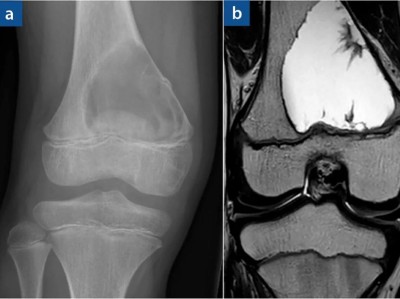

Schmerzbedingt kann ein 15-Jähriger sein rechtes Knie nur eingeschränkt bewegen. Seit etwa 3 Monaten verschlechtert sich die Symptomatik, insbesondere beim Sport. ASS bringt keine Besserung. Welche Diagnose stellen Sie? Zur Wahl stehen eosinophiles Granulom, Riesenzelltumor, Chondroblastom, Osteoidosteom, Osteomyelitis.